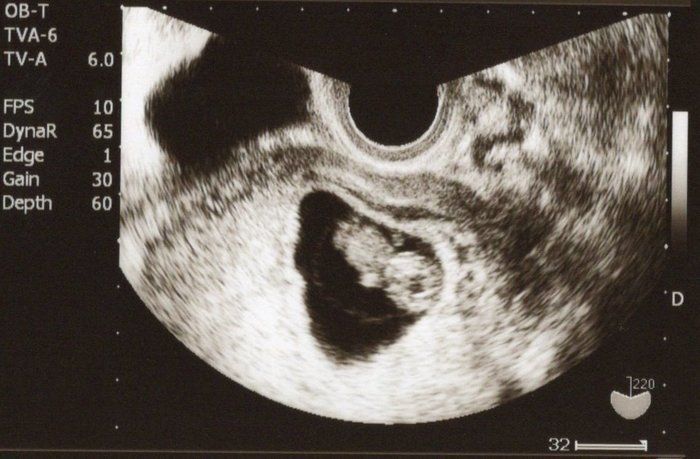

クリコさんの妊娠9週目のエコー写真

4D画像で頭、手、足を見ることができました。枝豆のような頭の形でなんだかかわいい、と早くも親バカ。この時期は、子宮がんや感染症の免疫の有無など、様々な検査を行いました。実母に、私がはしかやおたふく風邪にかかったかなどや、母がどのような妊娠・出産をしたかを教えてもらいました。